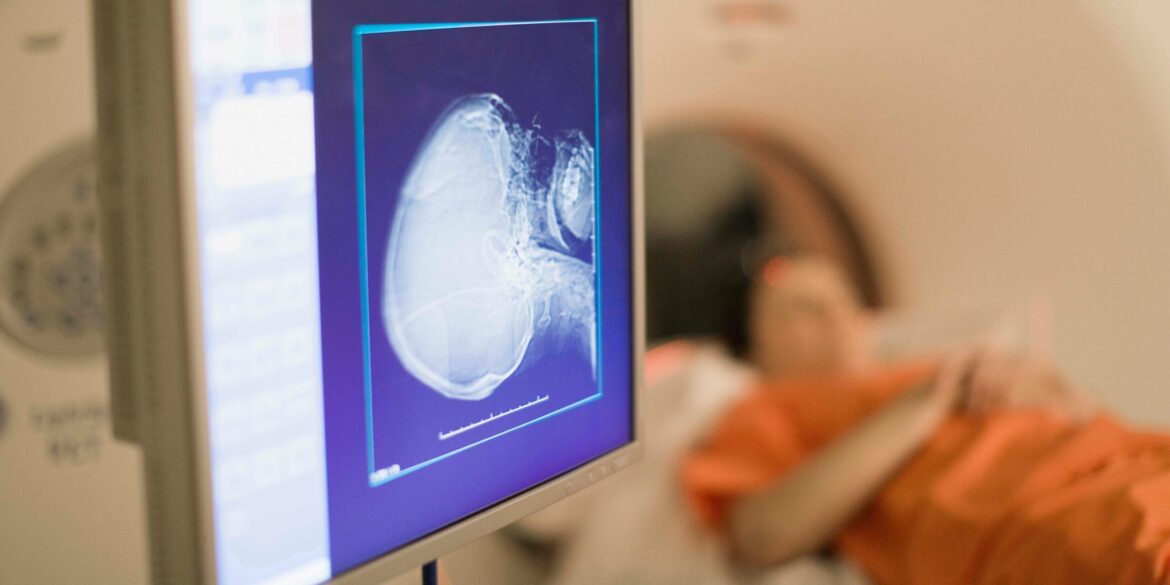

This new clinical trial at Mayo Clinic introduces a groundbreaking theranostic treatment. The term “theranostic” combines two important elements: “therapy” and “diagnostic.” The investigational radiopharmaceutical being used in this trial aims to target liver cancer cells with great precision, using diagnostic imaging agents to identify the tumors and then delivering therapeutic radiation directly to the cancerous cells. The unique combination of these two features provides a more focused and personalized approach to treatment, which is expected to reduce damage to healthy tissues and improve overall efficacy.

The dual capability of this treatment is one of the key innovations behind the trial. Diagnostic imaging is used to pinpoint the precise location of cancer cells within the liver, while the targeted therapy component delivers radiation directly to these cells, sparing surrounding healthy tissues. This targeted approach is a marked departure from traditional cancer treatments, which often affect both healthy and cancerous cells. By focusing only on the affected areas, this method holds the promise of not only improving the effectiveness of treatment but also reducing the side effects typically associated with more conventional therapies.